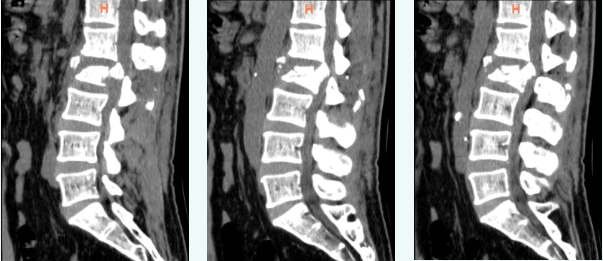

整个手术过程紧张有序,骨科三病区专家们凭借娴熟的技术和丰富的经验,精确地完成了每一个操作步骤。椎板减压环节至关重要,手术团队细致入微地处理骨折的碎片,确保脊髓不再受到压迫。随后,椎弓根螺钉的固定也为崔先生受损的腰椎提供了稳固的支撑,使其骨折部位得到了有效的固定和愈合的机会。

▲ 术后影像学检查